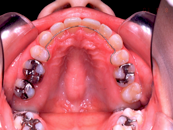

4) 治療に用いた装置 ストレートタイブマルチブラケットシステム(018x025スロット)

パラタルバー、前歯はセラミックブラケット

5) 抜歯 左右上顎第一小臼歯、下顎左右下顎第二小臼歯(計4本)

6) 治療期間 開始時から装置装着まで3か月、マルチブラケット期間2年3か月、保定期間4年